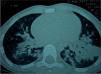

En la radiografía de control realizada a los 5 días del alta (13 días después del episodio de broncoaspiración) se aprecian imágenes aéreas de diferentes tamaños en ambos hemitórax, destacando una lesión cavitada en el pulmón izquierdo y otra en el derecho (fig. 3), por lo que se realiza TC torácica, que muestra imágenes quísticas parahiliares bilaterales, sugestivas de neumatoceles con nivel hidroaéreo en algunas de ellas (fig. 4). Ante el hallazgo radiológico y la reaparición de fiebre, la paciente reingresa para tratamiento antibiótico intravenoso, presentando evolución clínica favorable. En los controles posteriores permanece asintomática, con resolución radiológica total de los neumatoceles, aunque persiste una pequeña imagen residual de atelectasia en el lóbulo medio derecho.

La sintomatología inicial se caracteriza, al igual que otras neumonías aspirativas, por tos, dificultad respiratoria y dolor torácico, pudiendo presentar fiebre o en ocasiones escasez de síntomas1,3. El primer caso descrito presentaba mínima sintomatología, mientras que el segundo empezó con dificultad respiratoria progresiva y fiebre. Habitualmente, en la radiografía simple de tórax se observan infiltrados alveolares en uno o varios lóbulos, principalmente en zonas declives2,3, e imágenes “en vidrio deslustrado”. La TC puede mostrar condensación alveolar o imágenes de complicaciones pleuropulmonares como neumatoceles, nódulos fibróticos, derrames pleurales paraneumónicos, abscesos pulmonares o fístulas broncopleurales6,7. Como se puede observar en las imágenes, nuestro primer caso presentó una radiología típica sin complicaciones pleuropulmonares, mientras que el segundo desarrolló neumatoceles bilaterales que se resolvieron espontáneamente. Esta diferente evolución podría deberse a la distinta composición de la sustancia aspirada, al ser probablemente más lesivo el insecticida. En los casos con escasa clínica, debe realizarse un lavado broncoalveolar, donde se observan macrófagos cargados de lípidos en su interior, lo cual confirma el diagnóstico de neumonía lipoidea1,3,5. En nuestros pacientes no se realizó lavado broncoalveolar al considerar el antecedente de aspiración de sustancia lipídica y la clínica compatibles con el diagnóstico.